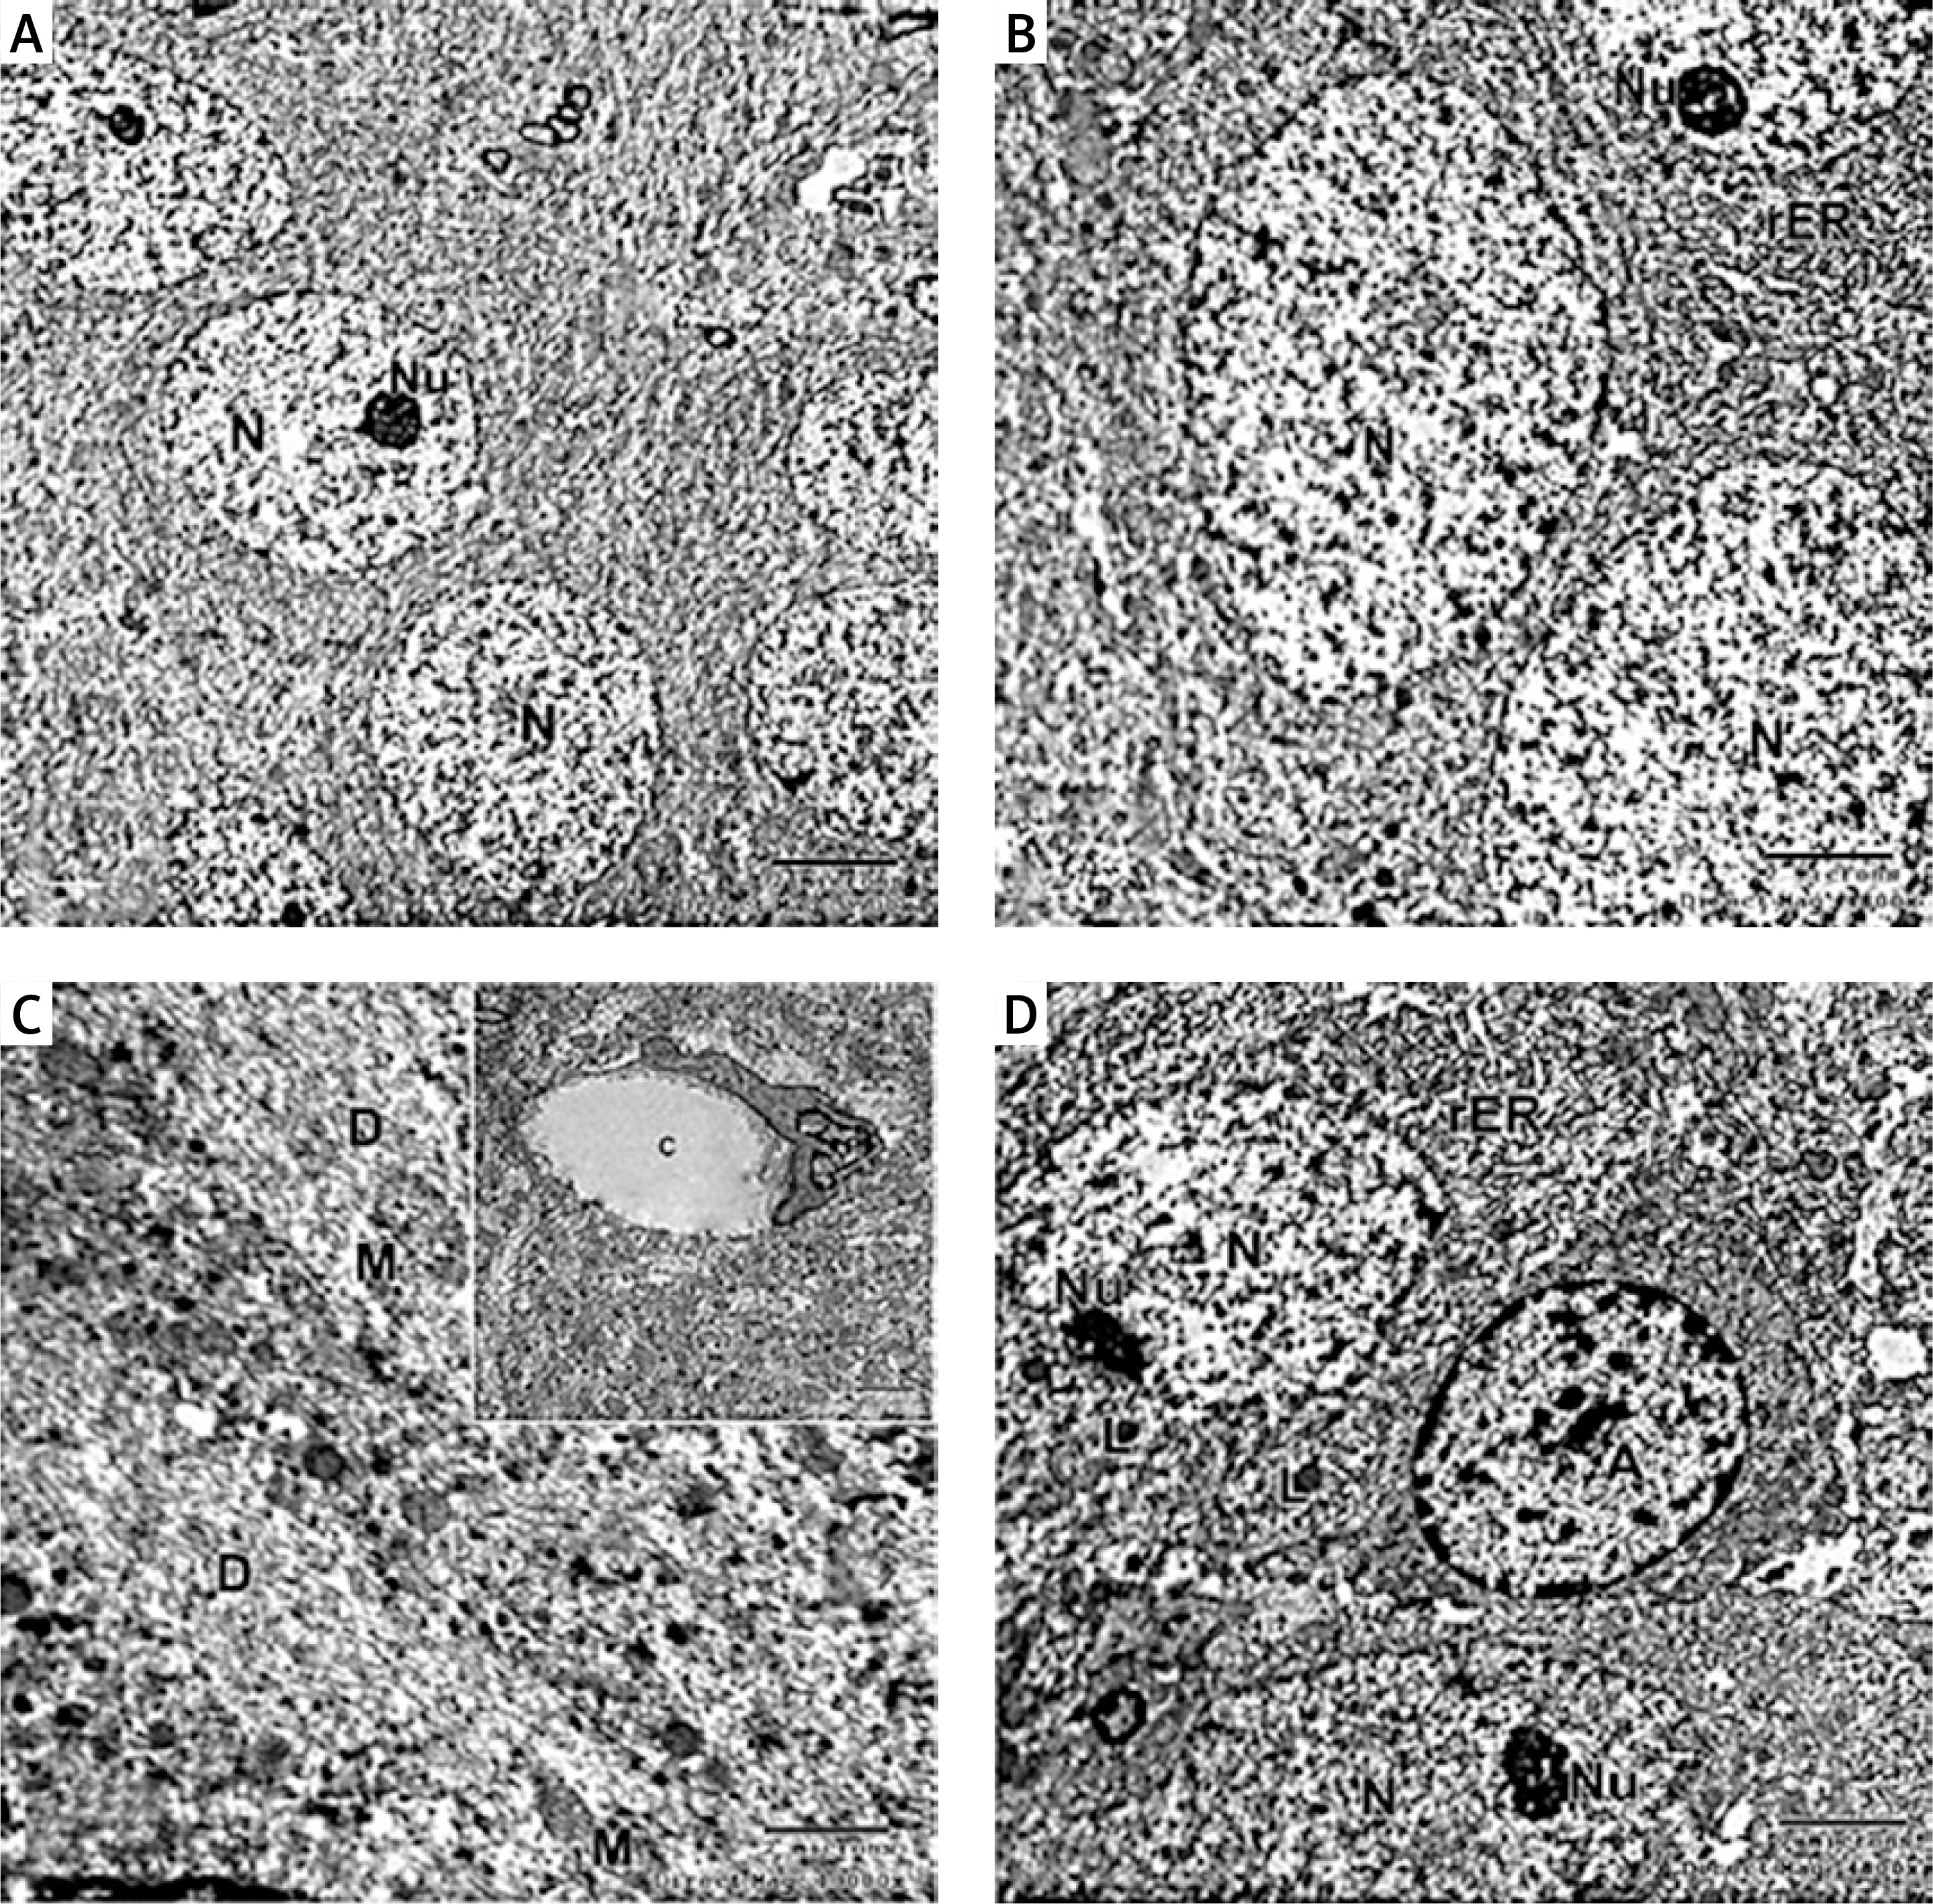

In the captopril-treated group, multiple neurons appeared normal with rounded euchromatic nuclei and nucleoli. The cytoplasm had numerous slightly dilated rER and multiple lysosome-like dense bodies (Figures 9 A, B). The dendrite exhibited well-organized microtubules, some mitochondria appeared normal oval, while others appeared abnormally elongated (Figures 9 C, D). The astrocytes appeared with dark nuclei and wide astrocytic processes, which also surrounded the blood capillary (Figures 9 C, D).

Figure 9

A – Electron micrograph of CA1 field of captopril-treated group showing 2 pyramidal neurons that appear fully normal (N) with rounded euchromatic nuclei and prominent nucleoli (Nu). Part of astrocyte (A) with dilated electron-lucent process (*) is present. Scale bar 2 µm and direct magnification 2900. B – A magnified part of the previous micrograph showing neuron with rounded euchromatic nucleus (N) and nucleolus (Nu). The cytoplasm has numerous slightly dilated (rough endoplasmic reticulum) and lysosomes (L). Scale bar 2 µm and direct magnification 4800. C – Electron micrograph of part of a dendrite (D) showing abnormally shaped elongated pointed mitochondria (arrow). Scale bar 2 µm and direct magnification 10000. The inset shows astrocyte (A) with wide electron lucent processes (*) and intact mitochondria (M). Scale bar 2 µm and direct magnification 5800. D – Electron micrograph of CA1field of captopril-treated group showing blood capillary (C) surrounded by wide astrocytic processes (*). The dendrite has well-organized microtubules and normal shaped oval mitochondria (arrow). Scale bar 2 µm and direct magnification 10000